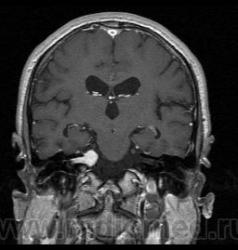

Пациент 35 лет, направлен неврологом из поликлиники с Ds: Рассеянный склероз? У данного пациента в течении года отмечается сильное головокружение и шаткость в походке, пришел на исследование на плечах у родственников. Данное исследование закачено на Dicom-сервер http: //www.radiomed.ru:8080/oviyam/oviyam? (под названием Brain-20101118).

Невринома правого слухового нерва

Если быть точным, VIII нерва;)

Более вероятнее невринома правого слухового нерва.